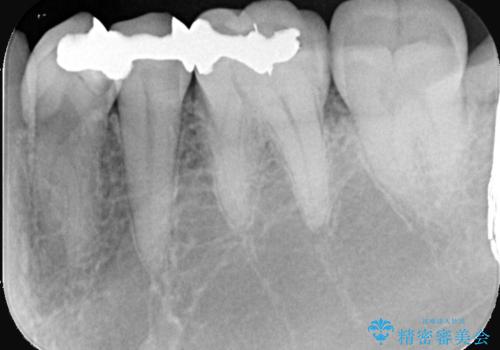

銀歯の下に虫歯 〈オールセラミッククラウン〉

- 初診時に金属の下に虫歯があることを指摘しました。もともとの詰め物の形と虫歯の大きさから被せものでの治療となりました。見た目、材質の説明をし、セラミッククラウンでの修復となりました。

メタルインレーが入っていたこと、う蝕が大きかったこと、頬側にHysに対してのCRがあったことを踏まえてクラウンでの修復を選択しました。